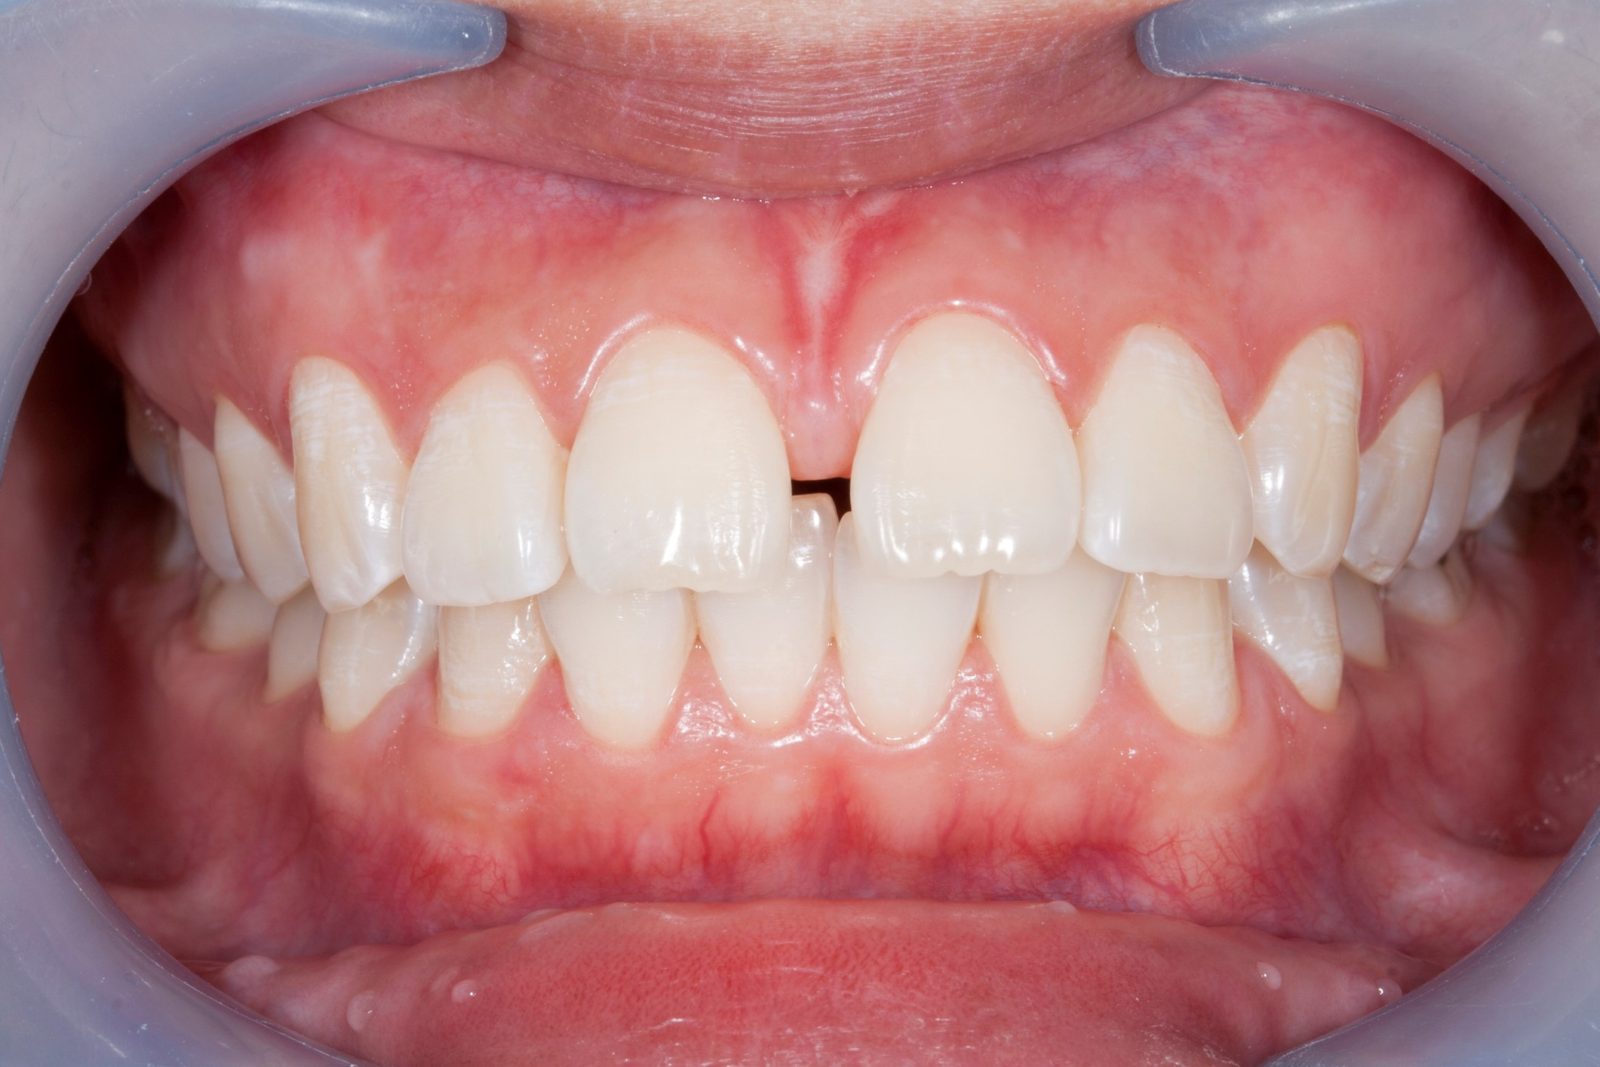

【主訴】歯のガタつき

【診断結果】叢生

【治療開始時の年齢】32歳

【治療内容】マウスピース型 (カスタムメイド) 矯正装置

【抜歯部位】上下左右4番目

【治療経過】後戻り無

【治療期間】2年4ヶ月

【治療費用】937,200円

【リスク・副作用】

治療初期の段階では痛みや不快感が生じる可能性がある。適切に歯磨きをしないと虫歯になる可能性が高くなる。個人差により予想された治療期間より長くなる場合がある。治療後はリテーナーを装着しないと後戻りしてしまうリスクがある。